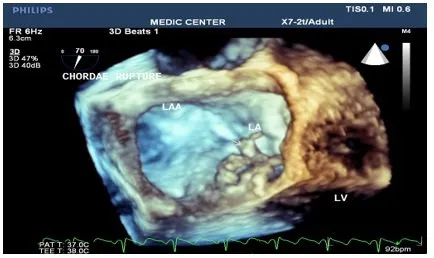

• Đánh giá bệnh lý van hai lá: Trong bệnh lý hở van hai lá, siêu âm tim 3D đóng vai trò quan trọng trong việc đánh giá mức độ hở, cơ chế hở và khả năng sửa van. Siêu âm 3D cũng được sử dụng để hỗ trợ sửa van hai lá qua da bằng thiết bị MitraClip.

• Hình ảnh cấu trúc 3D và chuyển động của tim: Siêu âm tim 3D cung cấp hình ảnh ba chiều về cấu trúc tim và chuyển động của các thành phần tim, đặc biệt là cấu trúc van tim. Điều này giúp bác sĩ hiểu rõ hơn về cơ chế bệnh sinh và lựa chọn phương pháp điều trị phù hợp.

• Hỗ trợ sửa van hai lá qua da (MitraClip): Siêu âm tim 3D đóng vai trò then chốt trong quá trình sửa van hai lá qua da bằng thiết bị MitraClip. Nó giúp bác sĩ đánh giá chính xác vị trí và mức độ hở van, hướng dẫn đặt MitraClip và đánh giá kết quả sau can thiệp. Siêu âm 3D khắc phục những hạn chế của siêu âm 2D trong việc đánh giá các thay đổi giải phẫu và hình thái trong và sau sửa van hai lá qua da.